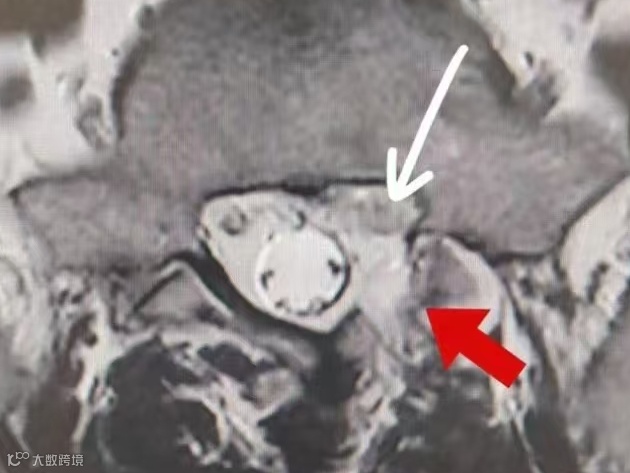

陈大爷术前影像学资料

陈大爷术后磁共振

70岁的陈大爷也遇到了和刘先生同样的情况,1年前无明显诱因出现腰部疼痛不适,自行在家休息后症状缓解,2周前弯腰劳作后出现腰部疼痛伴右臀部及下肢放射痛,持续加重,昼夜难眠遂被送来我院。检查发现患者脊柱、退变、骨质增生伴椎体不稳,多阶段椎间盘变性突出,详细查体后结合磁共振定位腰4/5为责任节段,骨科医师团队在路江鸿主任的带领下经过反复讨论认为,患者高龄,脊柱退变,本次发病为劳累后诱发腰4/5椎间盘急性突出相应神经根受压,开放手术对老人风险较高,决定行侧路椎间孔镜手术对患者较为合理。手术顺利,术后症状立即缓解,老人终于睡上了安稳觉。